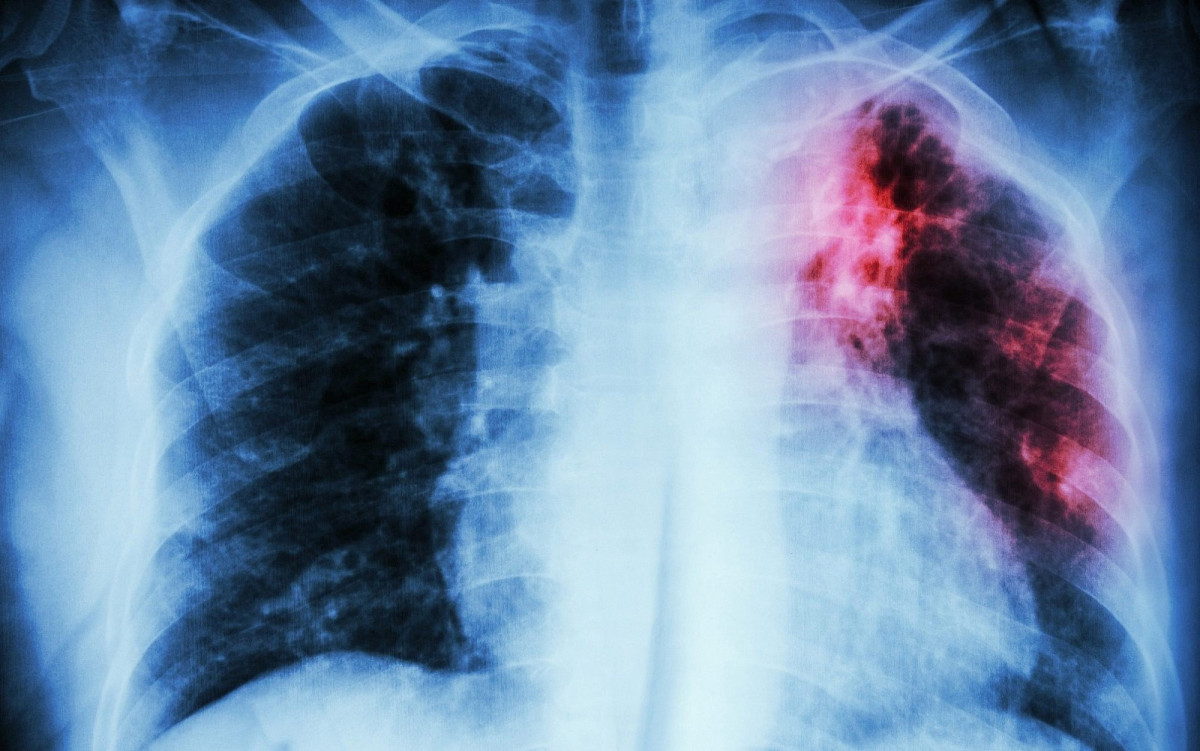

За 2023 год туберкулезом в Кузбассе заболели почти 1,5 тысяч человек По данным Роспотребнадзора, за 11 месяцев прошлого года с поставленным диагнозом «туберкулёз» в медучреждения региона попали 1428 человек.

В основном опасным вирусом заболевали взрослые люди. Зафиксированы и случаи, когда инфекцией заразились дети до 14 лет. Их оказалось 43. Почти 25% попали в больницу в возрасте с 15 до 17 лет (статистика составлялась исходя из заболевших, у которых обнаружили поражение легких впервые).

Что касается территорий, где было выявлено больше всего заболевших с начала 2023 года - лидером по заболеваемости стал Кемерово, где зафиксировали 318 случаев. На вторую строчку попал Новокузнецк с 245 заболевшими. Закрыл тройку антилидеров Прокопьевск, где выявили 96 случаев заражения.